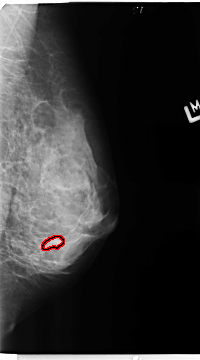

FILE: B_3359_1.LEFT_MLO.OVERLAY

TOTAL_ABNORMALITIES 1

ABNORMALITY 1

LESION_TYPE MASS SHAPE IRREGULAR MARGINS CIRCUMSCRIBED-OBSCURED

ASSESSMENT 4

SUBTLETY 3

PATHOLOGY BENIGN

TOTAL_OUTLINES 1

BOUNDARY